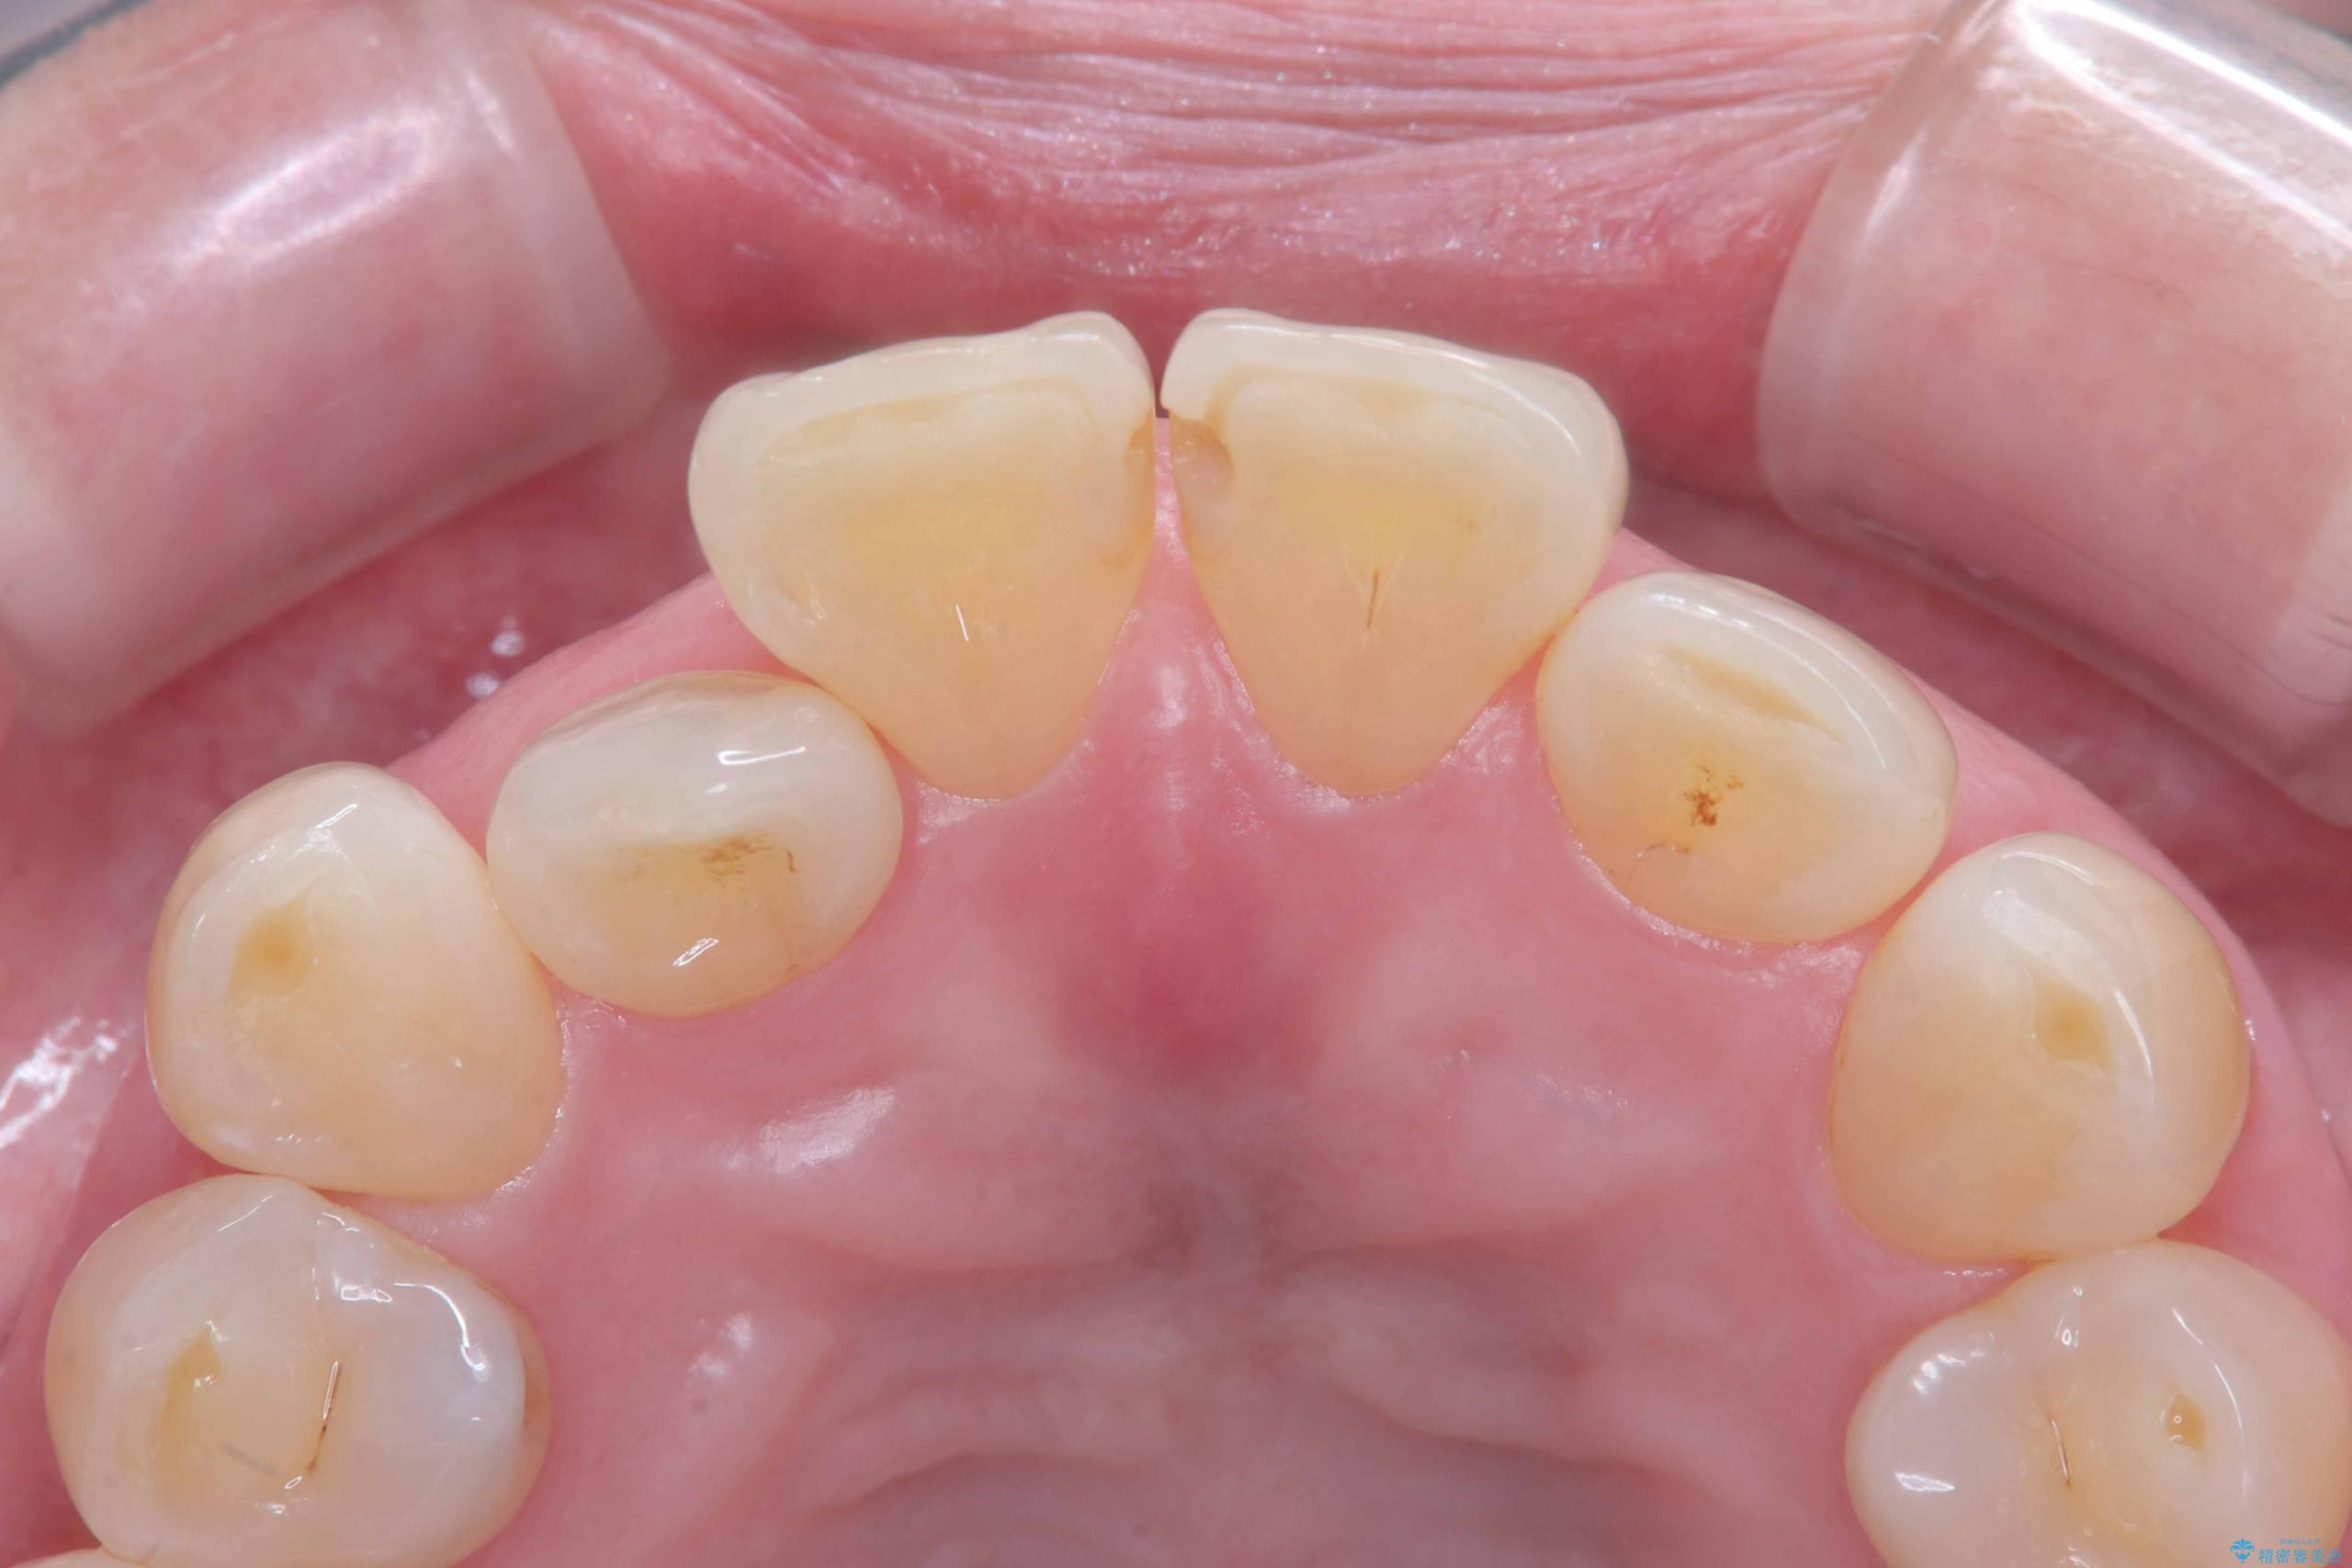

- 前歯の隙間とへこみが気になり、特に舌で触ると気になってストレスを感じるとのことで来院された患者様です。

上下ともに軽度の叢生があり、下顎がやや前突傾向にあったため、本来であれば矯正治療が第一選択となります。矯正によって下の前歯を後方に移動させることで、咬み合わせの改善とともに前歯のデコボコも整えることができます。

そのため今回は、右上2番を抜歯し、右上1番および左上1番をオールセラミッククラウンで審美的に修復しました。